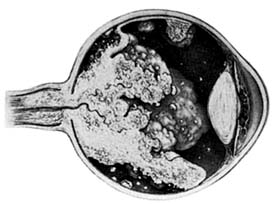

Retinal hemangiomas occur as isolated tumors or associated with cerebellar hemangioblastomas, pancreatic cysts and carcinomas, renal cysts and carcinomas, and pheochromocytomas in von Hippel-Lindau syndrome (Figure 10-30). The retinal tumors are pink or red, endophytic, and usually supplied by a large feeder vessel. Juxtapapillary tumors are usually exophytic. Vision is affected by bleeding or exudation from the tumor vessels. Photocoagulation, diathermy, and cryotherapy are used to treat the retinal lesions.

Figure 10-30

Figure 10-30: Angiomatosis retinae of Von Hippel-Lindau disease (drawing). (Courtesy of F Cordes.)